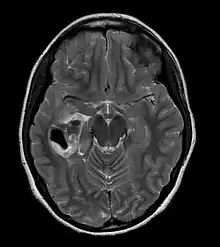

Pleomorphic xanthoastrocytoma | |

CT scan of a brain with pleomorphic xanthoastrocytoma. The classic radiographic appearance is one of a superficially situated tumor, here a mural nodule, associated with an underlying cyst. |